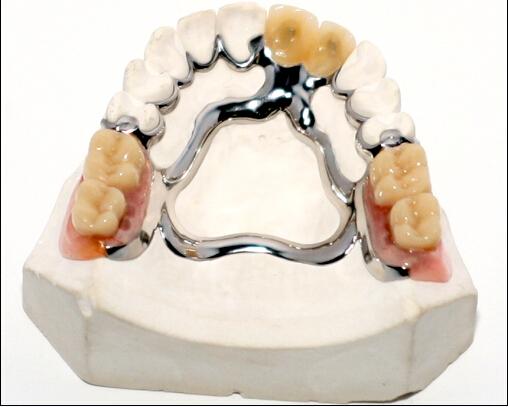

2.可摘局部义齿

是一种患者可以自行摘戴的牙列缺损修复体,利用天然牙、黏膜及骨支持,通过固位体卡环和基托将义齿固定在牙列内。恢复缺失牙及其周围缺损组织的解剖形态和生理功能。

与固定义齿比较,可摘局部义齿的优点是适应证广泛,很多不适合采用固定义齿修复的情况均可采用可摘局部义齿修复,比如缺失牙数目多、基牙牙周健康不理想、组织缺损等;可摘局部义齿的基牙不需要象固定义齿基牙那样大量磨除;可摘局部义齿的费用较固定义齿低,义齿损坏后可以修理,某些部位再缺失牙后可在原义齿上添加人工牙。

可摘局部义齿的缺点是义齿体积大,覆盖大量正常组织,初戴时常有恶心不适和发音不清,义齿与天然牙及组织间容易积存食物残渣和软垢,每天必须要反复摘戴义齿和清洁,否则影响余留牙的健康。